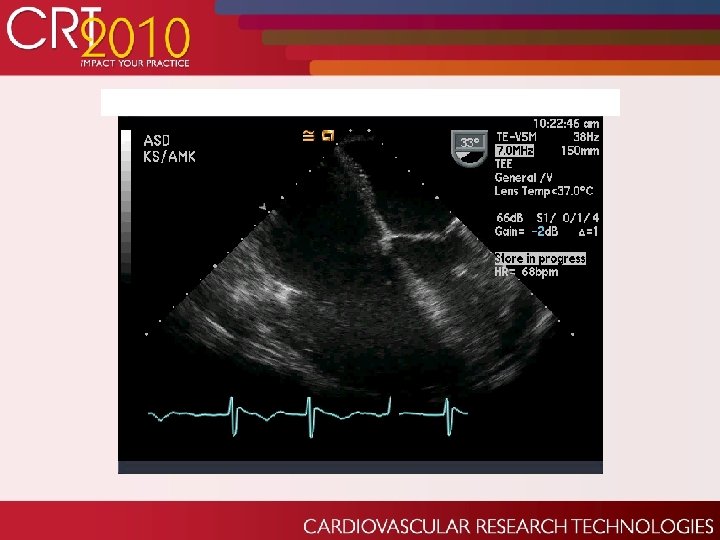

Echo post-surgical repair: